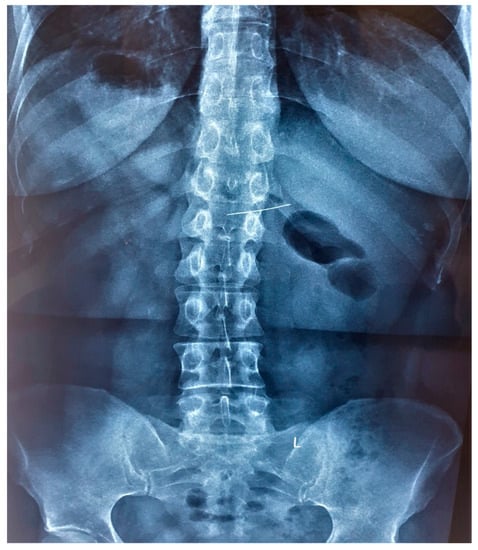

2. Case Presentation